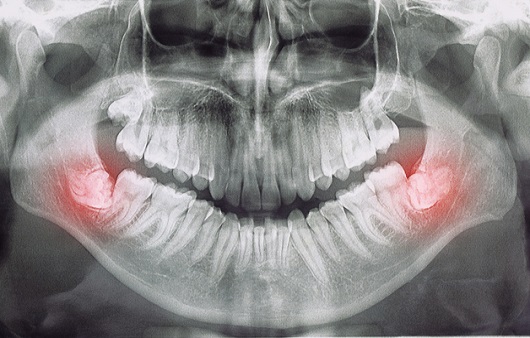

사랑니는 우리 입속에 가장 뒤에 난 어금니를 말하며, 전문용어로 설명해 드리면 제3대구치라고 하며 얼굴을 중심으로 좌우로 8번째 자리하고 있는 치아를 말합니다. 사랑니는 사춘기 이후에 자란다고 합니다. 사춘기에는 여러 가지 감정을 느끼게 되고 그 감정 중 하나가 사랑이라는 감정이지요. 그래서 이 치아를 사랑니라고 부른다고 합니다.

치과 치료를 하면 알 수 있는 것이 치아는 함부로 뽑지 않습니다. 정말 최대한 살려보고 그래도 안 되면 뽑아서 임플란트 등으로 빈자리를 채웁니다. 사랑니는 다른 치아들과 달리 발치를 해야 할 때도 있습니다. 잘 자란 사랑니는 특별한 문제를 일으키지 않아 뽑지 않아도 됩니다. 하지만 대부분의 사랑니는 말썽을 부립니다. 출혈, 염증, 통증 및 악취, 충치 들 여러 가지 문제를 일으킬 확률이 높기 때문에 뽑아야 합니다.